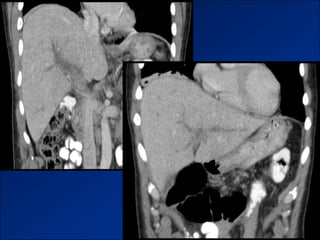

Tăng áp lực TMC

Dấu hiệu tăng ALTMC

Dấu hiệu tăng ALTMC– giả hạch mạc treo